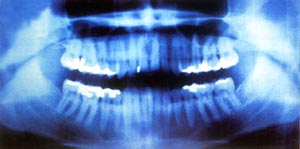

X射線公諸於世113年

X射線1896年1月5日,在柏林物理學會會議上展出了很多X射線的照片,同一天,維也納《新聞報》也報導了發現X光的訊息。這一偉大的發現立即引起人們的極大關注,並很快傳遍全世界。在幾個月的時間裡,數百名科學家為此進行調查研究,一年之中就有上千篇關於X射線的論文問世。

X射線是德國物理學家威廉·康拉德·倫琴在做一項試驗的時候偶然發現的。倫琴於1845年生於德國的倫內普。1869年,他獲得蘇黎世大學的哲學博士學位。在以後的19年中,他在多所大學工作過,贏得了優秀科學家的名譽。1888年起,倫琴任維爾茲堡大學物理學院教授和院長。